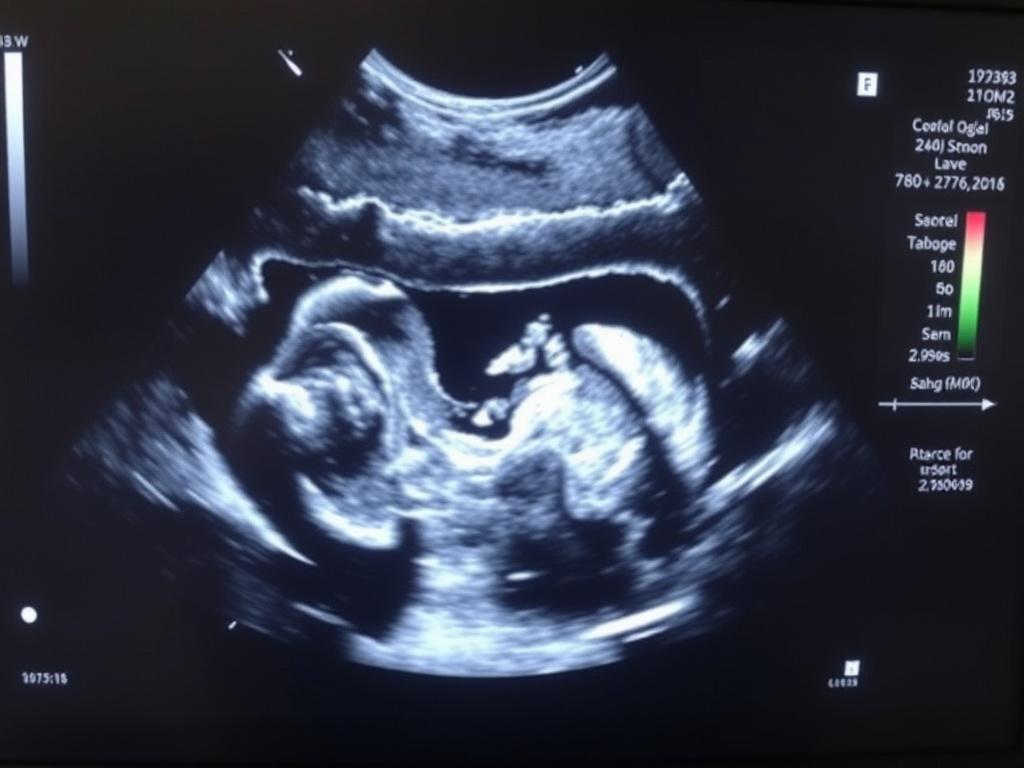

L’échographie morphologique (2ème trimestre) est souvent vécue comme un rendez‑vous charnière dans le déroulé d’une grossesse. Plus qu’une simple image, elle donne un aperçu précis de la construction de l’enfant à naître et oriente de nombreuses décisions médicales. Cet article explore en profondeur ce que couvre l’examen, ce qu’il peut révéler, ses limites et comment s’y préparer, avec des conseils pratiques pour patienter sereinement dans la salle d’attente.

L’objectif principal de l’examen est d’étudier l’anatomie du fœtus et de repérer d’éventuelles malformations visibles à ce stade de développement. Il permet aussi d’évaluer la croissance, la position du placenta et le volume de liquide amniotique, informations essentielles pour anticiper la suite de la grossesse.

La période idéale se situe généralement autour de la vingtième semaine d’aménorrhée, avec une marge courante entre 18 et 22 semaines selon les protocoles locaux. C’est le moment où les structures anatomiques sont suffisamment formées et néanmoins encore accessibles à l’imagerie ultrasonore.

L’examen se réalise le plus souvent par voie abdominale, le praticien appliquant un gel et parcourant l’abdomen avec une sonde. La durée varie : comptez en général entre vingt et quarante minutes, selon la coopération du fœtus, l’expérience de l’opérateur et la richesse des images à analyser.

L’exploration suit un protocole méthodique. Le praticien balaie successivement le crâne, le cerveau, la face, le rachis, le cœur, l’abdomen, les reins, la vessie, le cordon et les membres, sans oublier la localisation du placenta et l’estimation du liquide amniotique.

Chaque site fait l’objet de mesures standardisées et d’une analyse qualitative : présence, symétrie, contours et vascularisation. Le compte rendu précise les mesures biométriques et signale tout élément inhabituel nécessitant un complément d’examen.

Au‑delà de l’échographie 2D classique, l’imagerie 3D et 4D peut offrir des représentations plus réalistes du visage ou des membres, souvent utilisées à visée documentaire ou pédagogique. Ces techniques ne remplacent pas l’examen morphologique standard, mais elles enrichissent parfois l’analyse.

En parallèle, un examen normal apporte un soulagement concret. J’ai souvent constaté lors de ma présence aux côtés d’amies que la vision d’un petit visage ou d’un doigt qui bouge transforme l’angoisse en émerveillement, même si la prudence médicale demeure.

Je me souviens d’une matinée froide dans une clinique où j’accompagnais une amie : l’opérateur, calme et minutieux, a passé de longues minutes à chercher le bon angle. La première image du profil a déclenché un silence lourd, puis des sourires; ce souvenir illustre combien l’examen mêle science et émotion.